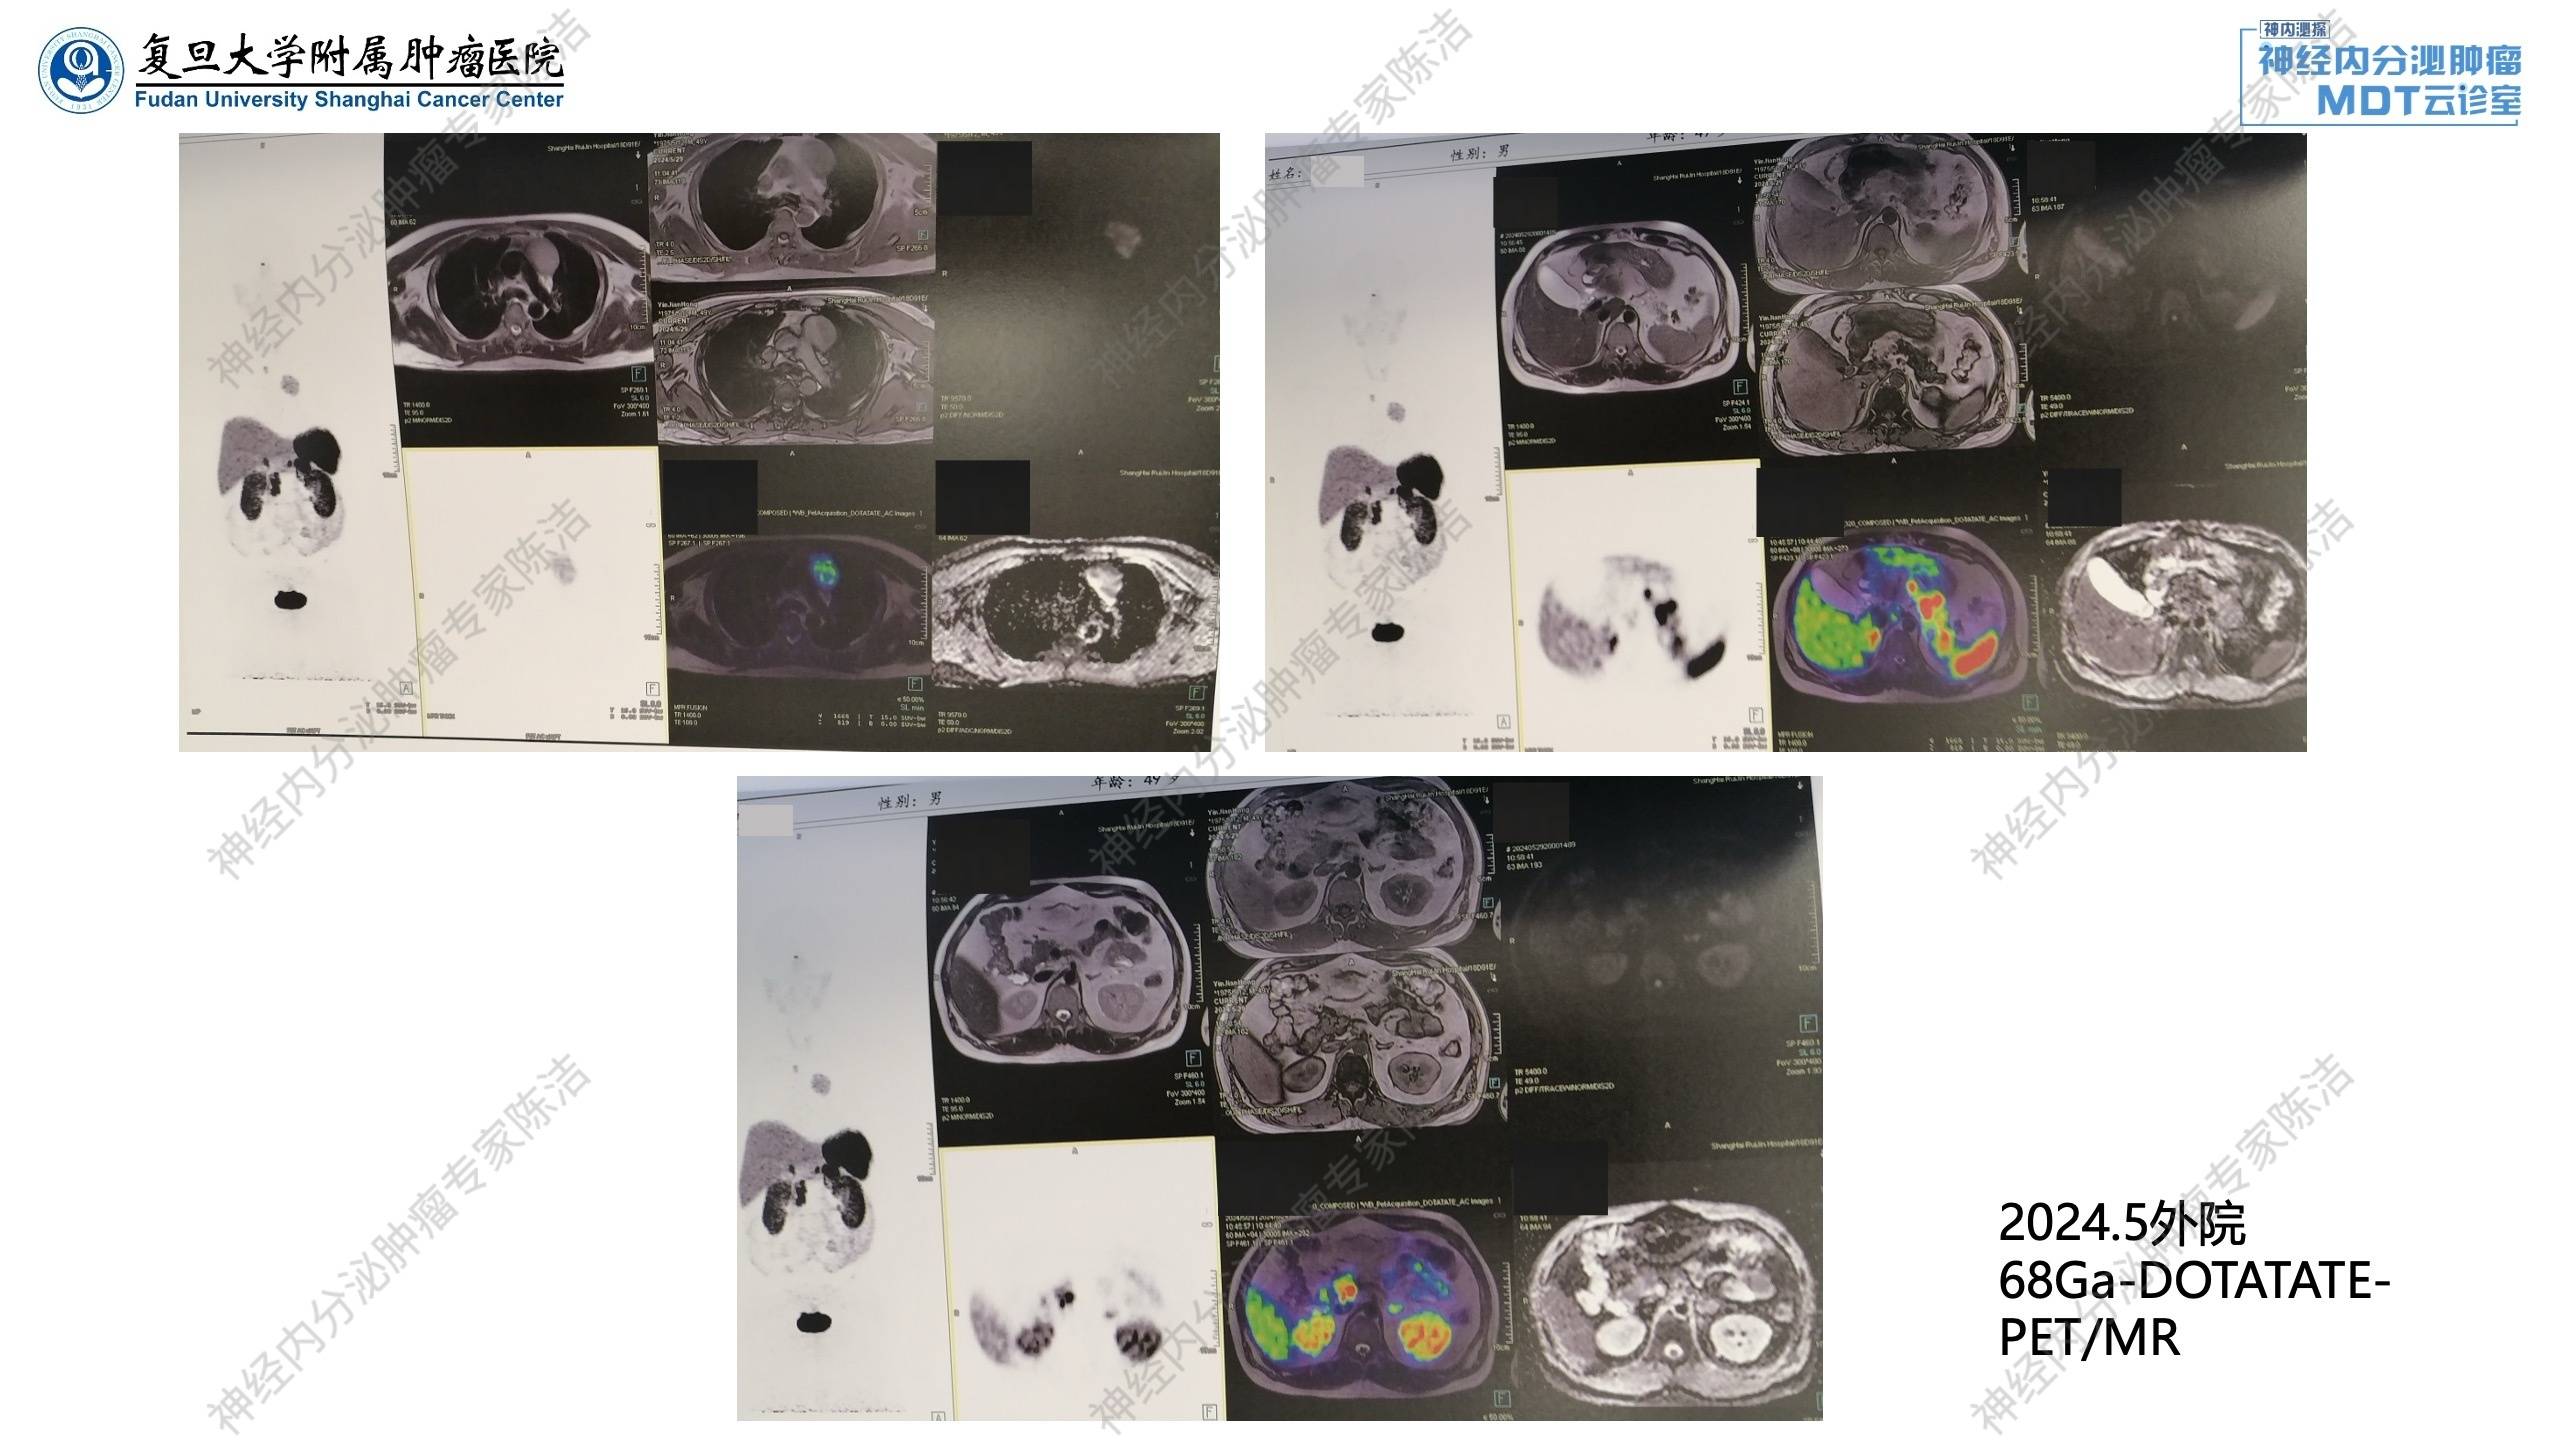

2024年5月:外院腹部增强CT发现胰腺多发囊实性占位,MEN-1可能。18F-FDG-PET/CT提示胰腺多发囊实性占位,增强后病灶边缘强化,代谢未见明显增高,考虑神经内分泌肿瘤可能;前纵隔异常信号灶,增强可见边缘轻度强化,代谢增高,恶性病变待排,胸腺来源?胸骨上窝肿大淋巴结,代谢增高,转移性病变不除外;胃粘膜皱襞宽大伴弥漫性代谢增高。

68Ga-DOTATATE-PET/MR提示胰腺多发囊实性占位,DOTATATE摄取增高,首先考虑多发胰腺神经内分泌瘤;前纵隔异常信号灶,DOTATATE摄取增高,结合FDG-PET考虑胸腺来源恶性病变可能,类癌?胸骨上窝异常信号灶,DOTATATE摄取增高,转移性淋巴结可能;左侧甲状腺上极背侧及左侧甲状腺下极点状DOTATATE摄取增高灶。

核医学科徐俊彦教授:外院FDG-PET提示前纵隔病灶显示清晰,糖代谢很高,且有区域淋巴结转移,但胰腺部位FDG低代谢。与之相反,DOTATATE-PET提示前纵膈病灶生长抑素仅轻度摄取,而胰腺可见多发生长抑素受体高表达病灶。考虑胰腺病灶及纵隔病灶为双原发神经内分泌肿瘤,结合病史,符合多发性内分泌腺瘤病1型表现。